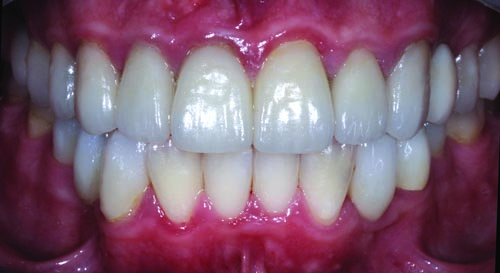

Fig. 33: Close-up retracted postoperative view of the definitive maxillary restorations, which included IPS E.max onlays, crowns and veneers.